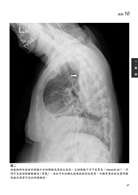

病例1 轉移性肉瘤(Metastatic sarcoma) 3